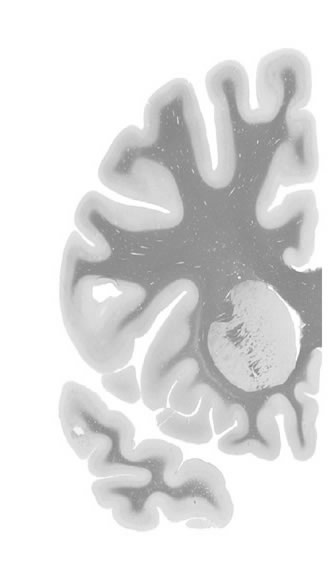

Frontal sections (Nissl) from the Atlas Brain: Gallery Slice Single

Macroscopy

-16,6 mm

Slice ID: r2-0470

Plate NR: 11

Position: -16,6 mm